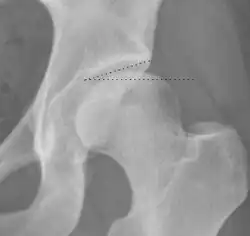

Radiograph of a pincer type impingement.

Projectional radiography ("X-ray") is often considered first line for FAI.[10] Anterior-posterior pelvis and a lateral image of the hip in question should be attained.[10] A 45-degree Dunn view is also recommended.[10][19]